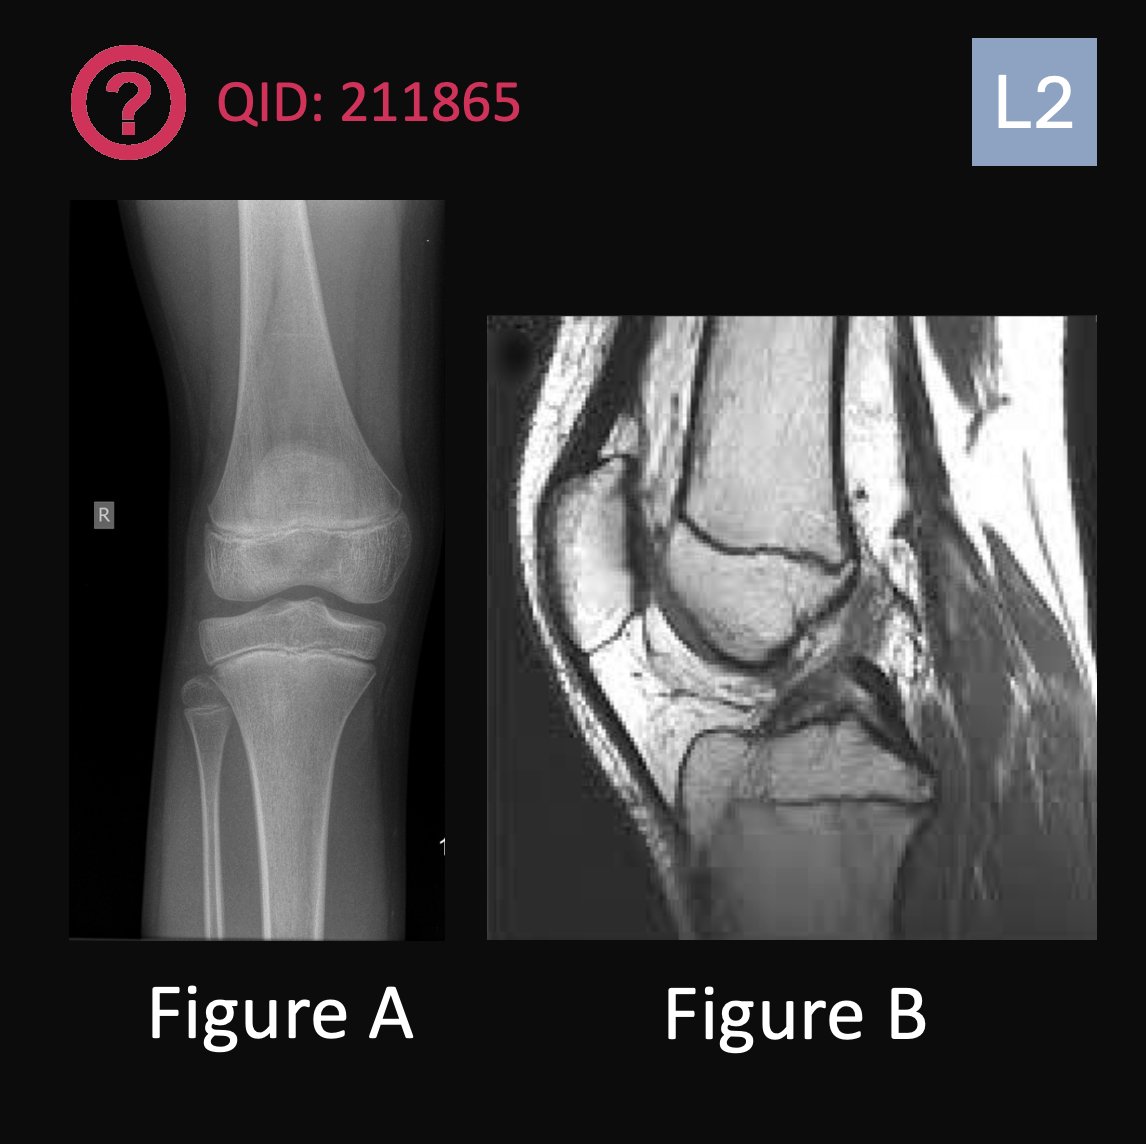

A 12-year-old female soccer player sustains a right knee injury when she made a sudden cutting move to intercept the ball. She noticed immediate pain and swelling with difficulty ambulating. On exam, she has a large effusion, a positive Lachman's test, and extension-flexion of the knee 20-70°. Figures A and B are the current imaging. What is the next best step in treatment for this patient?

1. ACL reconstruction with bone-patellar tendon-bone autograft

2. Physical therapy

3. ACL reconstruction with quadrupled hamstring autograft

4. Allograft reconstruction

5. Physeal-sparing iliotibial band tethering of lateral femoral condyle

QID: 211865

Comment your answer below, then check to see if you got it correct by clicking the link below to see the answer & explanation.

bit.ly/4c3C5tL